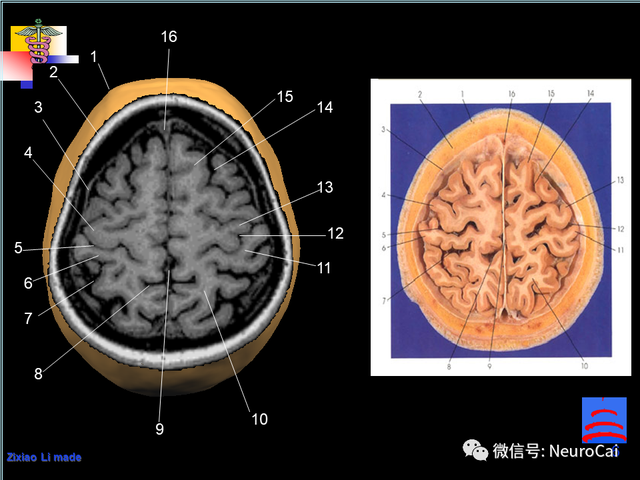

大脑结构图及功能图,人类大脑十大三维解剖图(脑局部解剖与功能图谱)